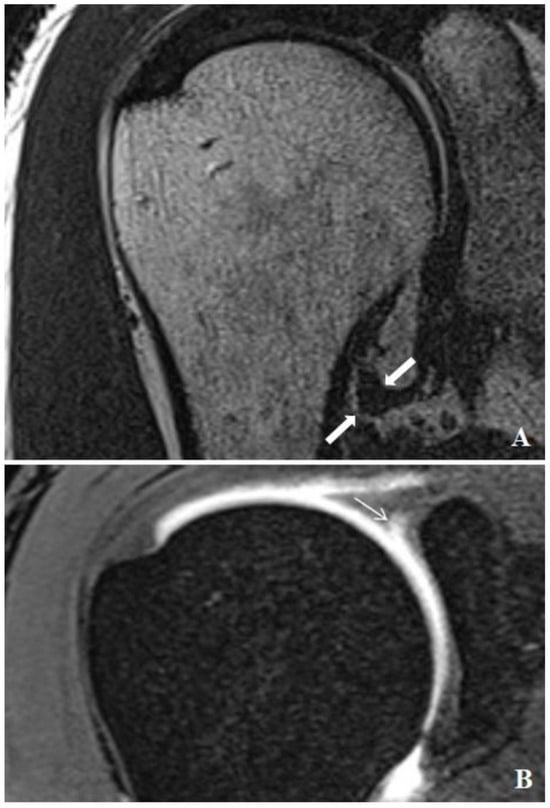

Relationship between SLAP Lesions and Shoulder Joint Capsule Thickness: An MR Arthrographic Study

2.2. Injection Technique, MR Arthrograms and Image Analysis